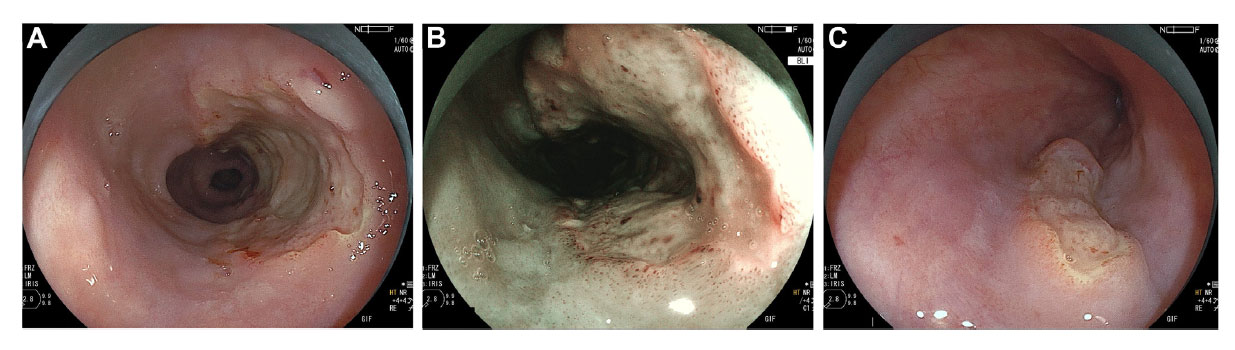

QUIZ: Ulcerating Esophageal Lesions